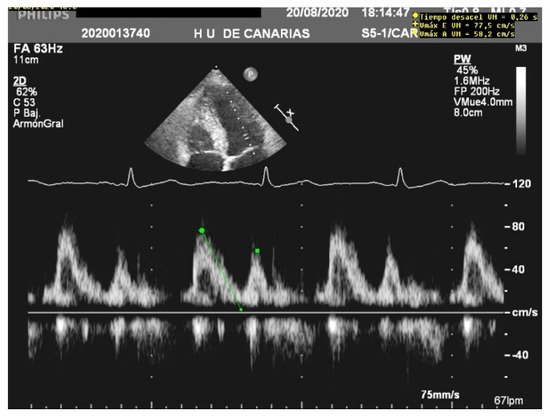

When assessing diastolic function, obtaining an E/e’ mitral ratio higher than 14.5 is associated with higher rates of weaning failure, even in atrial fibrillation [13][17][18], as are E waves higher than 0.87 m/s [13][19] ( Figure 1 ). However, this method is less reliable in acute decompensated heart failure and left ventricles with larger volumes, where significant mitral regurgitation can lead to underestimation, as well as in resynchronization therapy and wide QRS and the subsequent change in septal e’ due to its abnormal motion [20][21].